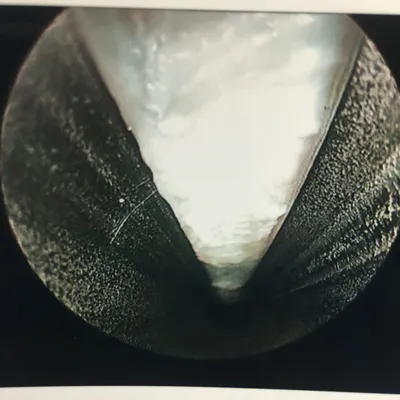

More Intraop Pics of Endoscopic Plantar Fascia Release. The thickened fascia is seen on the left. The Blade is cutting through the fascia in the center pic and confirmation of complete release of that portion of the ligament is noted as we can see the intrinsic muscles after release.